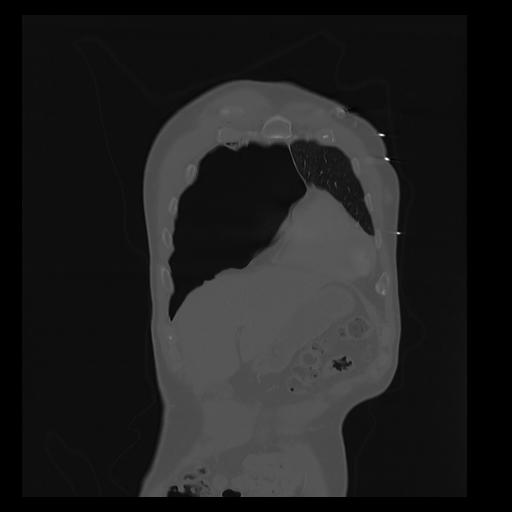

32 PULMON,CE,Coronal,3.000,PULMON,Coronal,